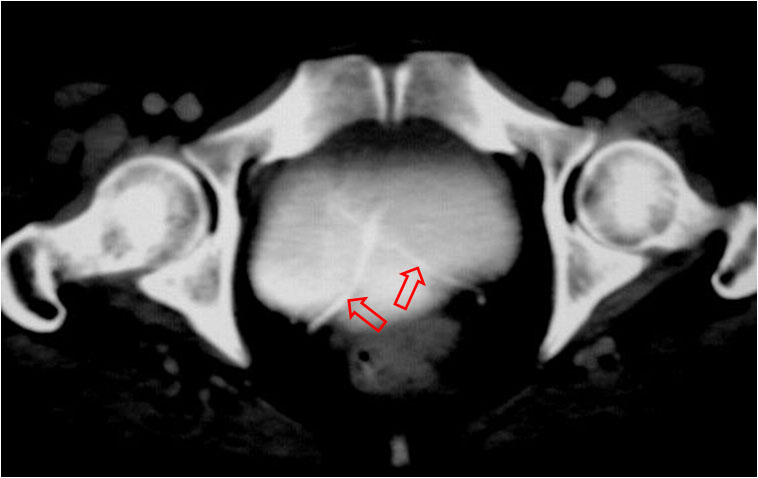

Signo visible en la urografía intravenosa o la cistografía de una mujer, correspondiente a una impresión en el suelo vesical similar a la impronta prostática del varón. Puede ser producida por lesiones neoplásicas o inflamatorias de la zona.

La imagen de TC corresponde a la misma paciente de la urografía, que presenta un tumor de cuello uterino -flechas negras- que infiltra la vejiga. Se trataba de un adenocarcinoma mucosecretor. La imagen recuerda a la impronta prostática en el TC.